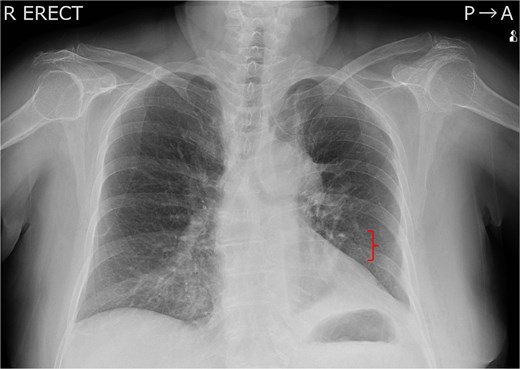

Robot-assisted left upper lobectomy using a portal approach was performed. A 12-mm port was placed near the sternum in the sixth intercostal space, and 8, 12, and 8 mm ports were inserted at the midclavicular, midaxillary, and scapular lines in the seventh intercostal space, respectively. An assistant’s 15 mm port was created near the costal arch in the eighth intercostal space, and CO₂ insufflation was performed at 6 Torr. The remote centre for the posterior port was positioned on the rib near the thoracic cavity, and the port positions were not altered intraoperatively (Fig. 1). The procedure included left upper lobectomy and mediastinal lymph node dissection. The operation time was 3 h, and blood loss was minimal. On postoperative Day 1, the patient presented severe wound pain, requiring two intravenous doses of pentazocine (15 mg) in addition to oral loxoprofen. Her oxygen saturation on room air was 93%. On postoperative Day 3, chest X-ray revealed a rib fracture on the dorsal side of the eighth rib (Fig. 2). On the same day, her SpO₂ improved to 97% on room air, and her respiratory status stabilized thereafter.

Chest X-ray taken on postoperative Day 3. A left 8th rib fracture was observed (bracket).